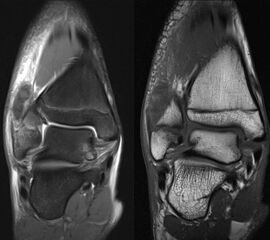

Osteochondrale Verletzungen

Osteochondrale Verletzungen können infolge eines Distorsionstraumas beobachtet werden (Taluskantenfraktur), teilweise lässt sich auch kein Trauma eruieren. Der es sich bei osteochondralen Verletzungen um keine Arthrose handelt, ist gerade bei Schmerzfreiheit ein defensives Vorgehen angezeigt. Bei offenen Wachstumsfugen kann eine osteochondrale Verletzung unter konservativer Therapie ausheilen.

Eine retrograde Anbohrung ist indiziert, wenn sich im MRT Verlauf eine zunehmende Sklerosierung im Randbereich der Läsion zeigt bei intakter Knorpeloberfläche.

Instabile Knorpelareale werden arthroskopisch entfernt in Verbindung mit einer Mikrofrakturierung der subchondralen Knochenlamelle.